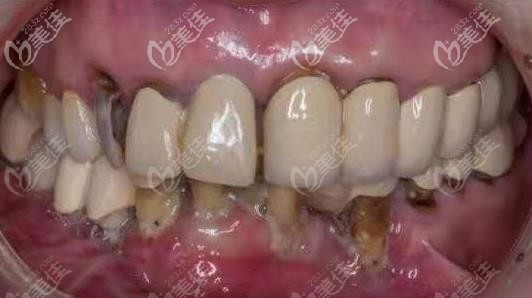

術(shù)前照片:

面診完醫(yī)生后,被告知我這烤瓷牙完全是不專(zhuān) 業(yè)的醫(yī)生做的,牙冠都沒(méi)有貼近,形態(tài)更是不符合真牙形態(tài),是個(gè)失敗,而且不僅如此,我的牙齒由于錯(cuò)誤的磨牙方法,導(dǎo)致牙齒受損較重,不能用了,只能拔除殘根殘冠做種植。